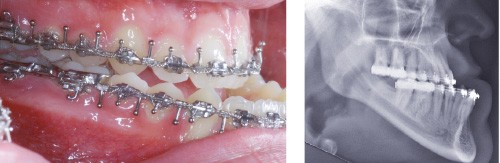

Les mouvements de décompensations sagittales et transversales sont réalisés à l’aide des tractions inter-arcades. La réévaluation céphalométrique et l’analyse des moulages confirment l’indication d’une chirurgie maxillaire de propulsion et d’une chirurgie mandibulaire par clivage bilatéral des branches montantes pour un recul mandibulaire modéré accompagné d’une génioplastie bidimensionnelle élargie qui rappelle la technique de Chin Wing.